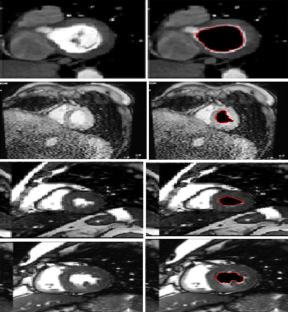

Segmentation of the left ventricle in MRI images is a task with important diagnostic power. Currently, the evaluation of cardiac function involves the global measurement of volumes and ejection fraction. This evaluation requires the segmentation of the left ventricle contour. In this paper, we propose a new method for automatic detection of the endocardial border in cardiac magnetic resonance images, by using a level set segmentation-based approach. To initialize this level set segmentation algorithm, we propose to threshold the original image and to use the binary image obtained as initial mask for the level set segmentation method. For the localization of the left ventricular cavity, used to pose the initial binary mask, we propose an automatic approach to detect this spatial position by the evaluation of a metric indicating object’s roundness. The segmentation process starts by the initialization of the level set algorithm and ended up through a level set segmentation. The validation process is achieved by comparing the segmentation results, obtained by the automated proposed segmentation process, to manual contours traced by tow experts. The database used was containing one automated and two manual segmentations for each sequence of images. This comparison showed good results with an overall average similarity area of 97.89%.

Fig. 1

Fig. 2

Fig. 3

Fig. 4

Fig. 5

Fig. 6

Fig. 7

Fig. 8

Fig. 9

Fig. 10

Fig. 11

Fig. 12